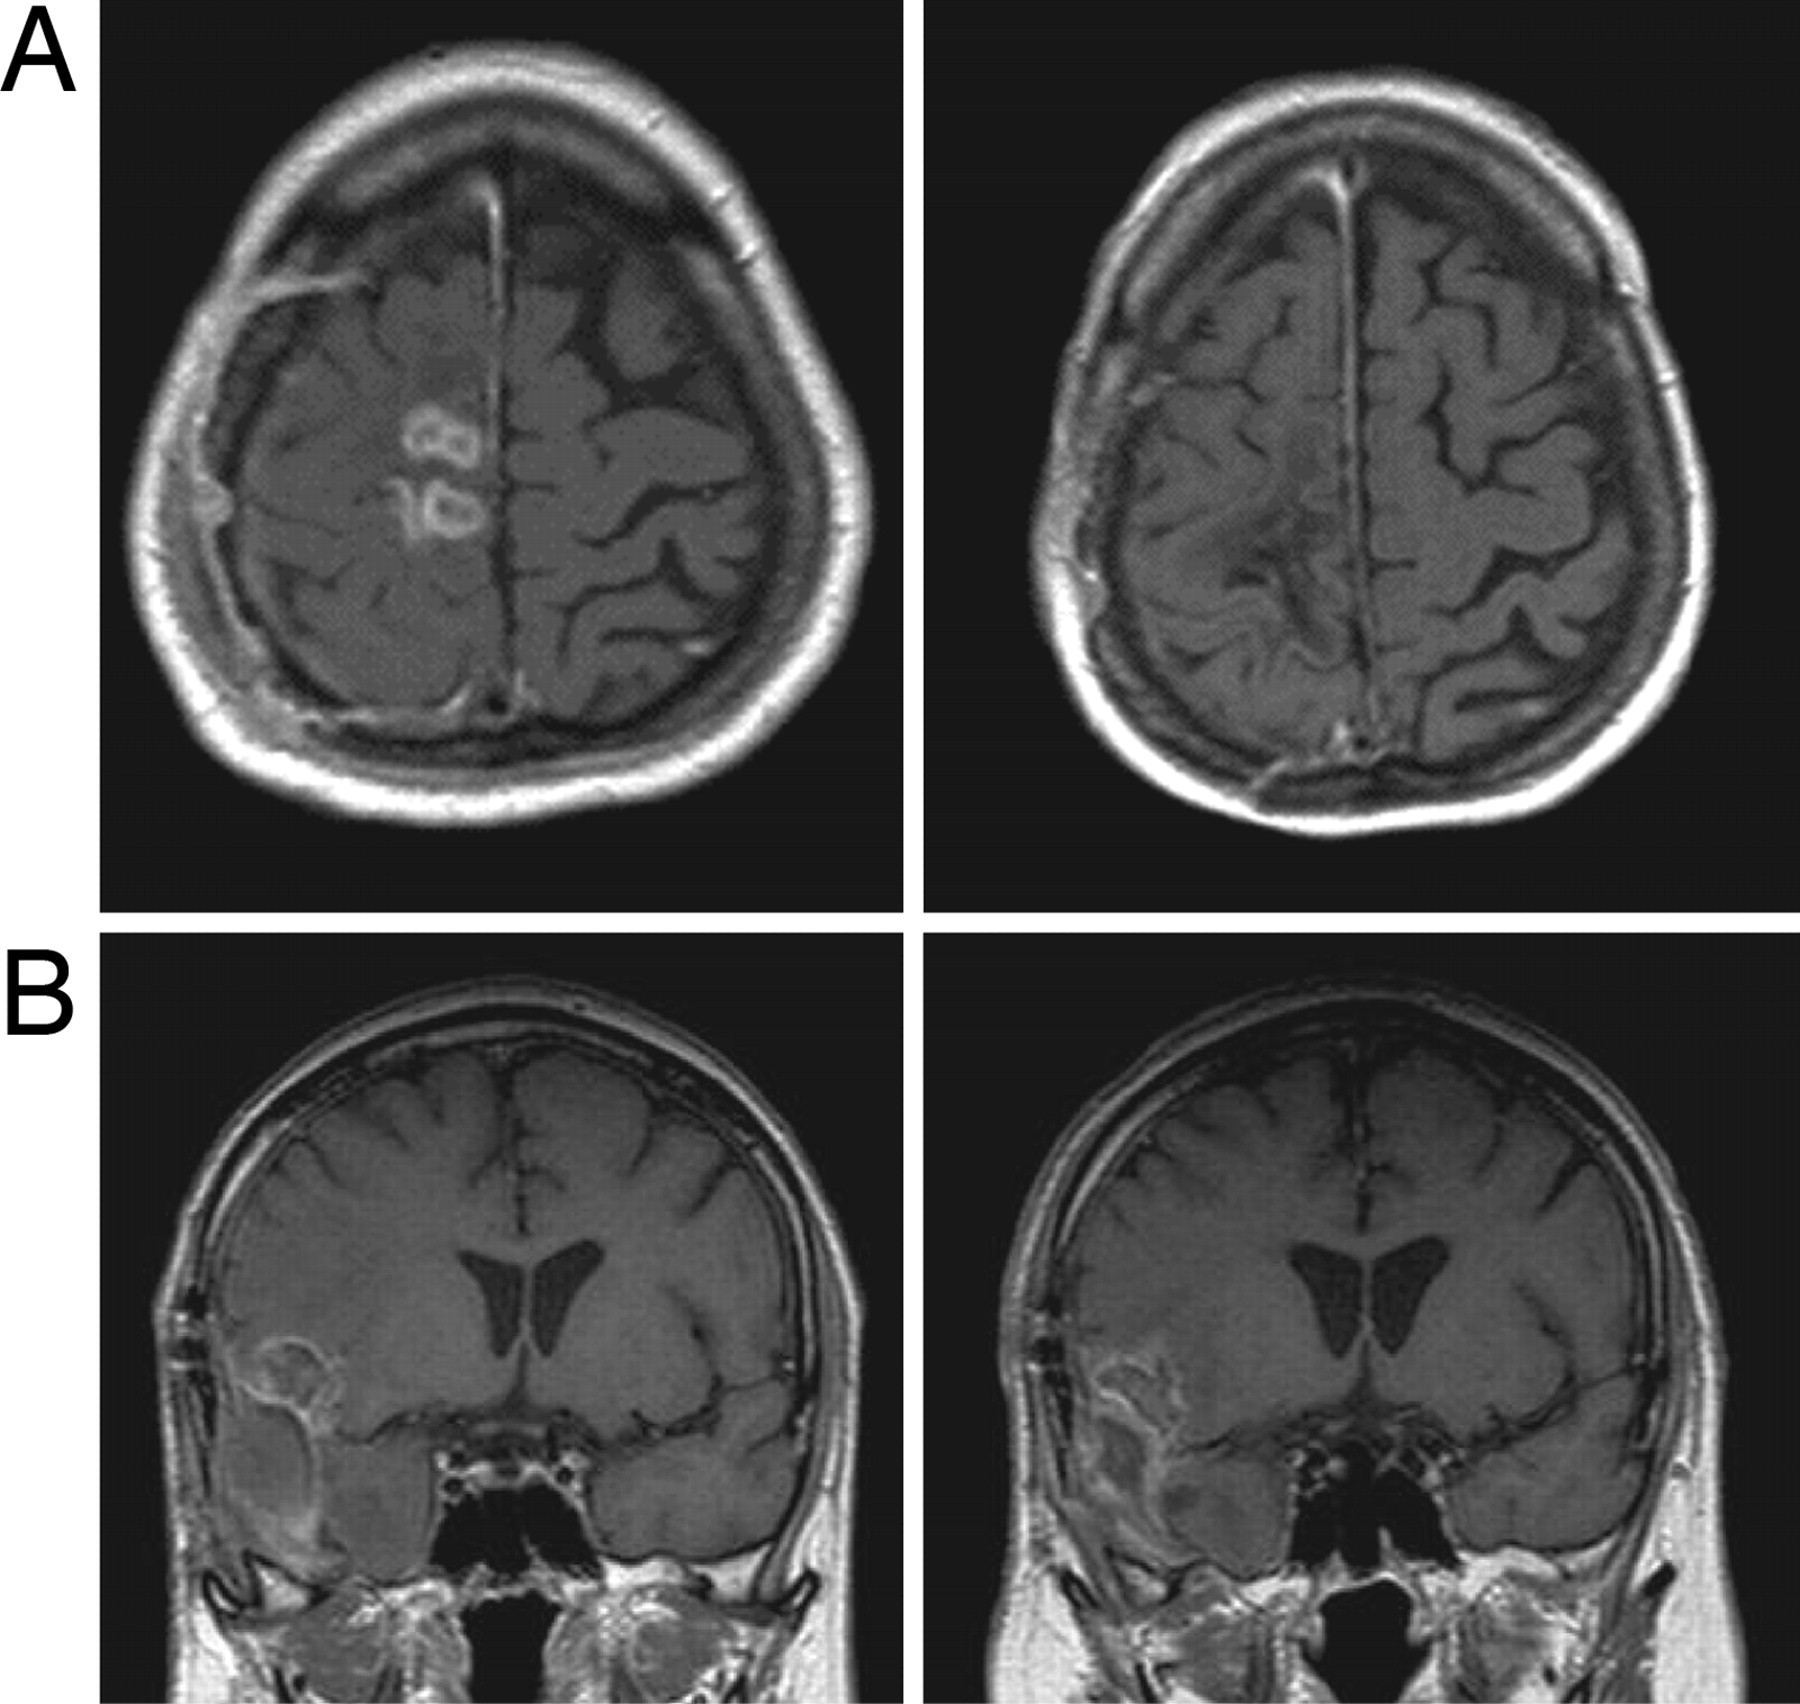

Conclusa la raccolta di fondi per finanziare un nuovo studio clinico sul dispositivo Novo-Ttf* per il trattamento del glioblastoma multiforme, il tumore maligno cerebrale più comune e più aggressivo. Il device utilizza campi elettrici a bassa intensità e appositamente regolati (Tumor Treating Fields – campi Ttf) per interrompere la divisione delle cellule tumorali. Ad annunciarlo è NovoCure, società privata israeliana specializzata in dispositivi medici innovativi contro il cancro. I campi Ttf, generati da elettrodi applicati sulla superficie del cuoio capelluto – spiega una nota – agiscono sulle cellule cancerose in rapida divisione e le distruggono, o fanno sì che non si dividano correttamente; al contrario, le cellule sane, che non si dividono, non vengono influenzate.